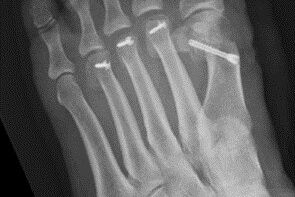

Therapie: distale Umstellung am MT1, Osteotomie an MT 2-4

Die operative Korrektur, bei der Umstellungsosteotomien an den Mittelfußknochen 1-4 links durchgeführt wurden, erfolgte im Mai 2018.

Bei anhaltenden Beschwerden wurde im Mai 2019 eine Röntgenaufnahme durchgeführt, die einen Schraubenüberstand von 1mm am Köpfchen des MT3 ergab. Dieser Befund wurde durch eine CT Untersuchung, bei der zusätzlich eine Arthrose im Grundgelenk der Großzehe und der zweiten Zehe gefunden wurde,  bestätigt.

Röntgenuntersuchungen